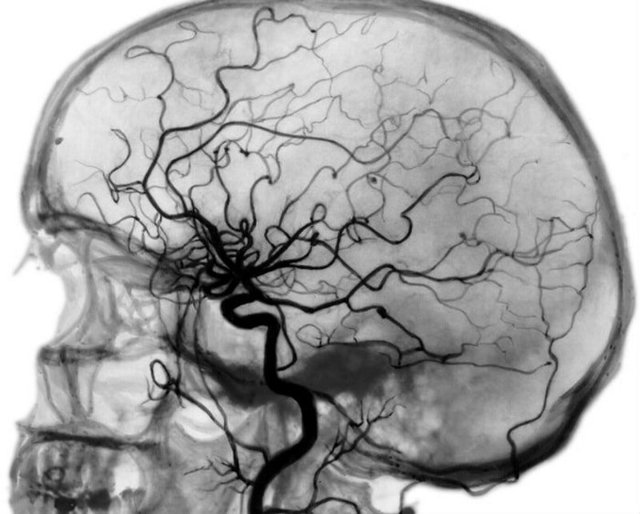

- Под традиционной ангиографией сосудов головного мозга подразумевают рентген головы после контрастирования сосудистой сетки мозга с применением контрастных средств.

- Процедура осуществляется методом пункции или катетеризации экстракраниальных и интракраниальных сосудов, внедрением лекарства и последующего вывода фотографий.

Церебральная ангиография — это рентгенологический метод визуализации сосудов головного мозга, который заключается в окрашивании сосудистого русла введенным предварительно контрастом.